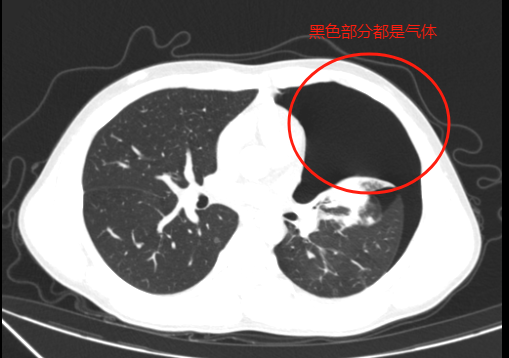

CT影像显示气胸已压缩肺组织达50%以上。

急诊科医生迅速为小江安排了胸部CT检查。结果显示,小江是自发性气胸,有多发肺大疱,肺组织已经被压缩了一半,当即将他收治到心胸外科。心胸外科主任王杰接到值班医师通知,得知情况危急,需立即进行穿刺排气,迅速赶到医院,带领团队为小江实施了胸腔闭式引流术。术后,大量积气被成功引流出,暂时缓解了症状。